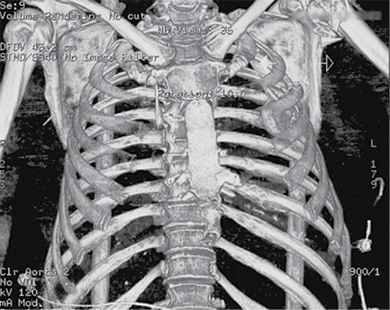

Figure 2. Subsequent 3D reconstruction